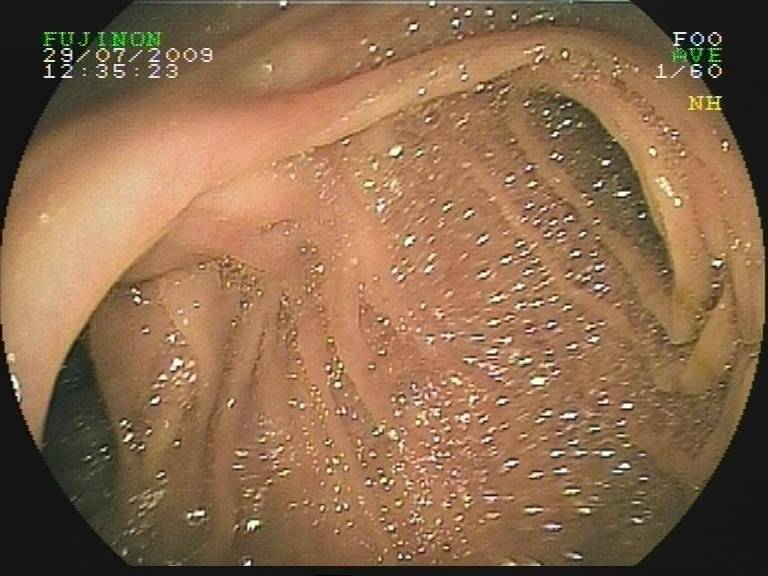

胃镜检查:食管胃底静脉曲张

小肠镜检查:胆肠吻合口多发血管扩张,空肠吻合口息肉。

胆肠吻合口迂曲的血管

胆管壁迂曲的血管